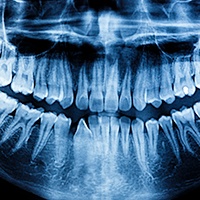

After your cleaning, Dr. Preet Taneja will give your mouth a thorough exam. The main goal of this exam is to detect any dental issues that may have occurred since your last appointment. She will check your mouth, head, neck, and jaw to make sure everything is functioning well, and she will also use digital X-Rays to get an in-depth look at your teeth. X-Rays are typically where she will be able to identify tooth decay and cavities. She also prevents and detects issues like:

Some patients are wary of X-rays because they bring to mind radiation levels. However, thanks to our modern technology, there’s nothing to fear. We take all our X-rays digitally, which reduces radiation exposure by 90% while giving us clearer, faster images of your teeth and jawbone. We’ll always give you a lead apron to drape over the rest of your body as well to completely minimize your risk.